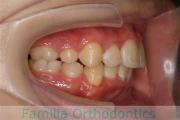

No.22V-299

- 上顎前突

- 叢生

- 30歳

- 女性

- 上:

- 44

- 下:

- 主な使用装置:

- FEA 022

- 治療にかかった費用:

- 90万円

上の出っ歯、口が閉じにくい、下の前歯のガタガタを治したいということで来院されました。上顎から左右小臼歯を、下の前歯は凹凸が非常に強いので、こちらから一本抜歯を行いました。2年強、30回程度の通院が必要でした。

成人になってからの叢生(でこぼこ、凹凸、ガタガタ)は、保定をしっかりしないと後戻りをしてしまうリスクが高いです。